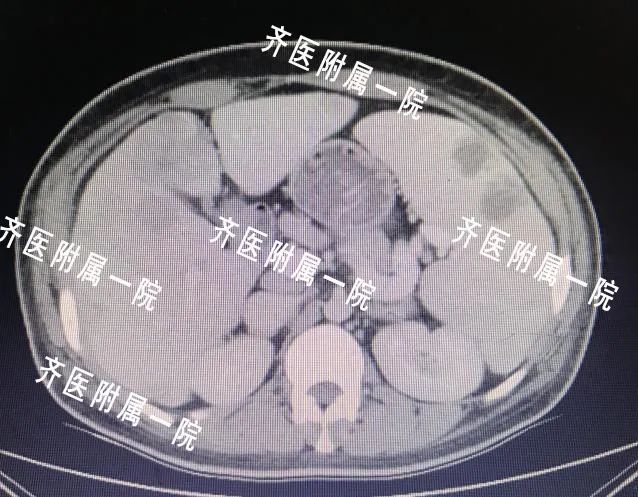

近年来肿瘤的发病年龄越来越年轻化,大家已经开始逐渐重视它。穿刺活检是肿瘤治疗过程中非常重要的一步,肿瘤患者需要选择那些手段治疗,往往有赖于穿刺活检得到的病理结果。首先:看片子做出的诊断叫做“影像学诊断”,只能凭经验初步判断是不是肿瘤,但是具体是哪一种类型的肿瘤,有没有基因突变都不得而知,后面的治疗用药也会盲目。所以,穿刺以后得到的病理结果是医生确诊的金标准,比如下面肿瘤科的这个患者:

这个年轻的患者如果当时不去做穿刺活检,就会被当成一个肝转移骨转移的晚期肿瘤患者对待,经过穿刺活检,提示他只是一个肝脏结核造成的骨破坏,所以说病理活检是多么必要!